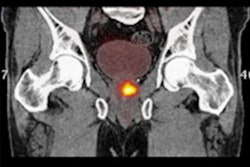

Negative prostate-specific antigen (PSMA) PET scans can be used to avoid unnecessary pelvic lymph node dissection in certain prostate cancer patients undergoing radical prostatectomies, according to a recent study.

To that end, the researchers investigated whether PSMA-PET scans -- which have a high negative predictive value (NPV) in determining whether cancer has invaded lymph nodes -- can be used to avoid unnecessary procedures in men with intermediate-risk disease.